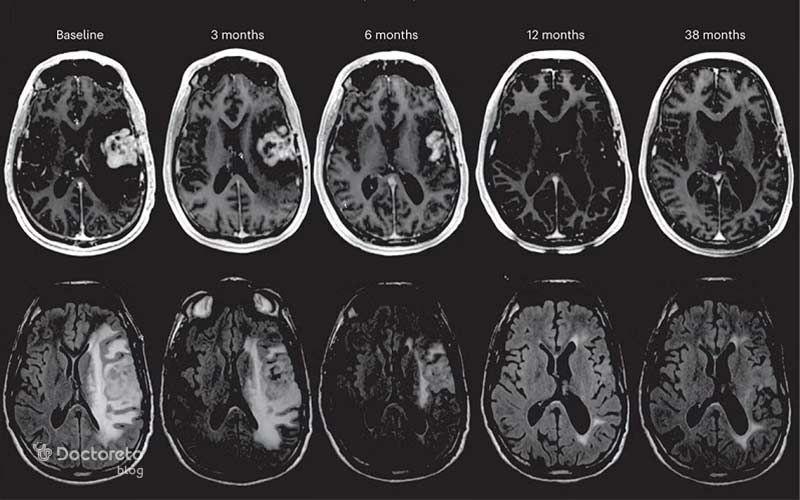

درصد بسیار نادری از بیماران بدون انتظار قبلی، کاهش چشمگیر یا حتی توقف کامل تومور را تجربه میکنند. این پدیده که در اصطلاح پزشکی «پسرفت خودبهخودی» نامیده میشود اغلب به دلیل فعال شدن ناگهانی سیستم ایمنی رخ میدهد. مطالعهای در Journal of Neuro-Oncology (۲۰۲۰) نشان داد که تعداد بسیار کمی از این بیماران پس از یک عفونت ویروسی یا تب بالا، کاهش قابل توجه تومور داشتند؛ زیرا سلولهای ایمنی T بهطور مؤثر سلولهای سرطانی را هدف قرار میدهند.

ایمونوتراپی (درمان تقویت سیستم ایمنی بدن) در سالهای اخیر به عنوان یکی از روشهای درمان تومور مغزی مطرح شده است. در کنار آن، پیشرفت در جراحیهای دقیق مبتنی بر نقشهبرداری مغزی نیز به افزایش احتمال موفقیت در حذف کامل تومور کمک کرده است.

در جهان، چندین مطالعه علمی به بررسی موارد نادر «پسرفت خودبهخودی» تومورهای مغزی پرداختهاند. این پدیده در حدود ۱ درصد بیماران مشاهده میشود و اغلب در بیمارانی رخ داده که سیستم ایمنی آنها پس از عفونت یا واکسیناسیون خاصی فعال شده است.